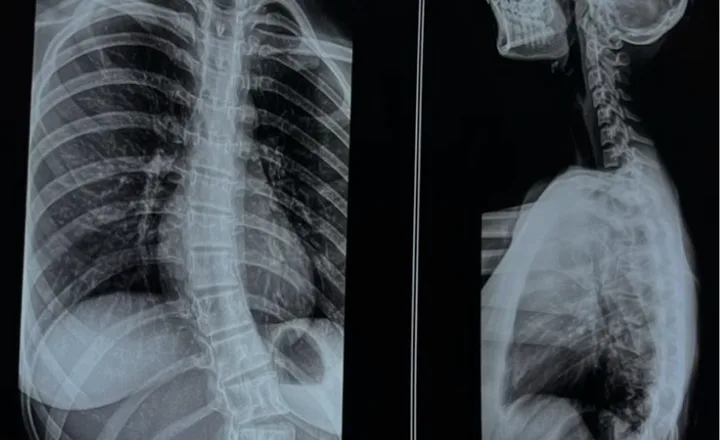

Introduction to Spinal Cord Injury

Spinal cord injury (SCI) is a neurological condition that occurs when damage to the spinal cord influences communication between the brain and different parts of the body. The functional impact varies depending on the injury level, severity, and individual health factors, often affecting mobility, sensation, or coordination. Long-term management commonly includes structured rehabilitation programs, physiotherapy, and assistive support strategies.

A spinal cord injury can result from trauma, compression, or medical conditions affecting spinal tissues. Depending on the injury location, individuals may experience variations in movement, muscle strength, sensory perception, or autonomic function. Because every injury profile is unique, multidisciplinary care involving neurologists, rehabilitation specialists, and physiotherapists is typically recommended to support long-term functional goals.